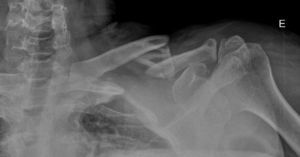

En cuanto a la consolidación se refiere, ésta se consiguió con un tiempo medio de 14 semanas (8-42 semanas). Para la evaluación radiológica de la consolidación de la fractura se observó el paso de puentes óseos entre los fragmentos de fractura (fig. 4). En 7 casos se solicitó además una tomografía computarizada para la confirmar la consolidación.

Dentro de las complicaciones, dos casos (5,8%) presentaron un retraso de la consolidación. Uno de ellos acabó consolidando y el otro desarrollo una pseudoartrosis con aflojamiento de la placa, requiriendo una nueva reintervención con la colocación de una nueva placa y aporte de injerto autólogo de cresta ilíaca. Estos casos de retardo de consolidación y pseudoartrosis coincidían con pacientes intervenidos más de tres semanas después de la fractura.